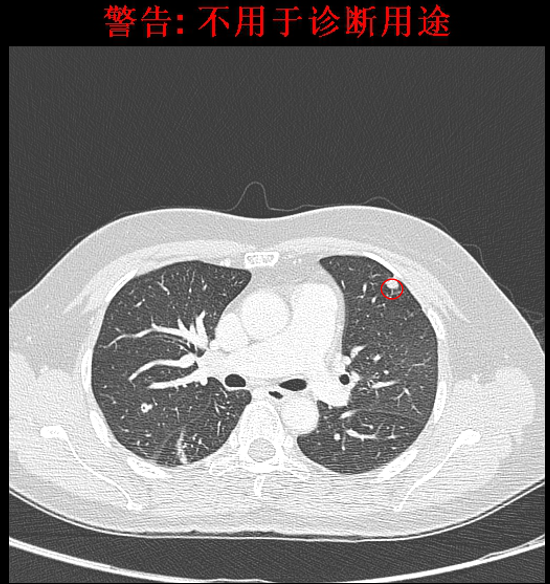

2016-4影像